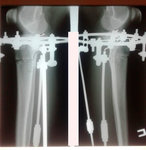

Дата операции - 07.11.2019г.

Дата снятия аппаратов - 15.02.2020

Срок сращения 92 дня.